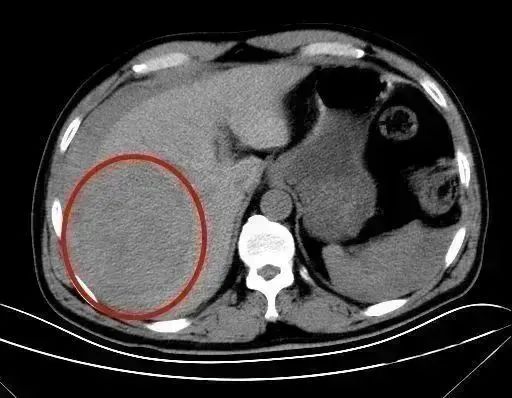

急救团队结合CT检查诊断,肝脏巨大肿块破裂、腹腔大量积血,万分危急。

【CT影像下的巨大肿块】

“患者肝脏肿块的直径约10公分,足有铅球大小,肿块包膜破裂引发了大出血。”放射科副主任郑胜解释,慢性乙肝患者有可能发展成肝硬化甚至肝癌。当肿瘤在腹腔内生长受限时,就会突然破裂出血。